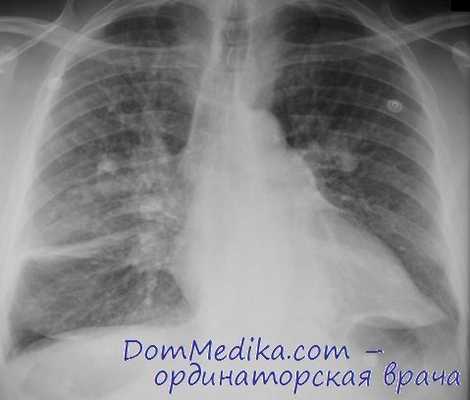

Рентгенологическое исследование пневмокониозов. При пневмокониозах определяют мелкие округлые или неровные затемнения на рентгеновском снимке. В более тяжелых случаях пневмокониоза и силикоза могут находить распространенные затемнения, которые не характерны при асбестозе. При пневмокониозе (у работников угольной промышленности) и силикозе увеличивается преимущественно количество округлых теней в средних и верхних отделах, тогда как асбестоз характеризуется наличием мелких, неправильной формы теней в нижних отделах.

Пневмокониозы с крупными участками затемнения (рис. 16-2) разделяют на классы следующим образом:

• класс А — участки затемнения с наибольшим диаметром от 1 до 5 см или несколько участков затемнения с диаметром каждого более 1 см, но сумма их наибольших диаметров не превышает 5 см;

• класс В — один или несколько более крупных, по сравнению с классом А, участков затемнения, чья общая площадь не превышает таковую правой верхней доли;

• класс С — один или несколько участков затемнения, общая площадь которых превышает таковую верхней правой доли.

В I стадии симптомы могут отсутствовать либо быть представлены быстрой утомляемостью, кашлем, одышкой при физических усилиях и болями в грудной клетке. По данным рентгенографии в средних отделах легких определяются мелкоочаговые тени диаметром от 1 до 3-5 мм; корни легких расширены; легочный рисунок деформирован.

Для II стадии антракоза типична одышка в покое, нарастание общей слабости, сохранение кашля и торакалгии. Рентгенологические изменения включают увеличение числа и размеров мелкоочаговых теней, выраженную эмфизему, утолщение плевры.

III стадия антракоза протекает с выраженными признаками дыхательной недостаточности. При прогрессирующем массивном фиброзе может наблюдаться меланофтиз – откашливание мокроты черного цвета, обусловленное прорывом фиброзных каверн в дыхательные пути. Тяжелыми осложнениями прогрессирующей формы антракоза служат легочная гипертензия с правожелудочковой недостаточностью. На рентгенограммах легких определяются отдельные массивные затемнения размером до 5-10 см на фоне множественных мелкоочаговых образований и феномена «медовых сот». Иногда в центре крупных теней видны антракотические каверны.